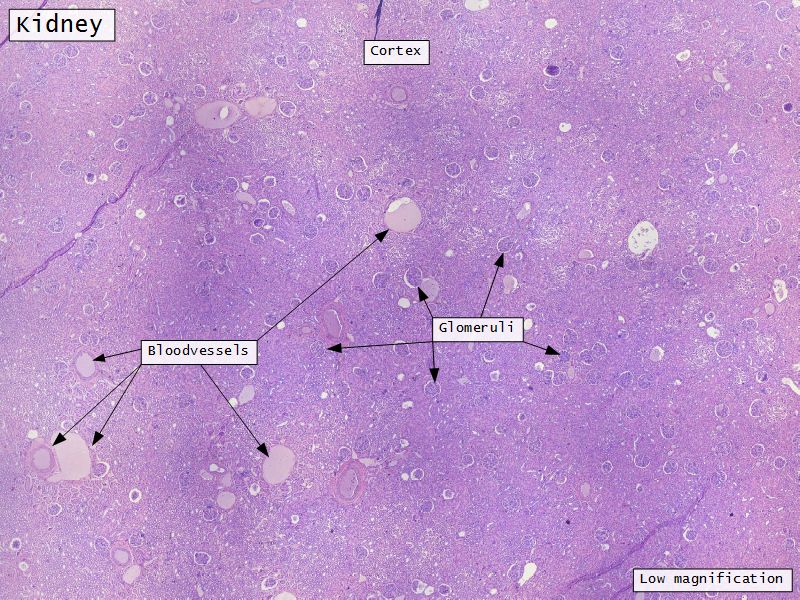

Appearance

- Cortex

- Renal corpuscles

- Convoluted tubules

- Medulla

- Loops of Henle

- Collecting tubules

Kidney lobule

- Group of neprons

- Open into branches

- Same collecting duct

- Not clearly demarcated

- Interlobular arteries/veins